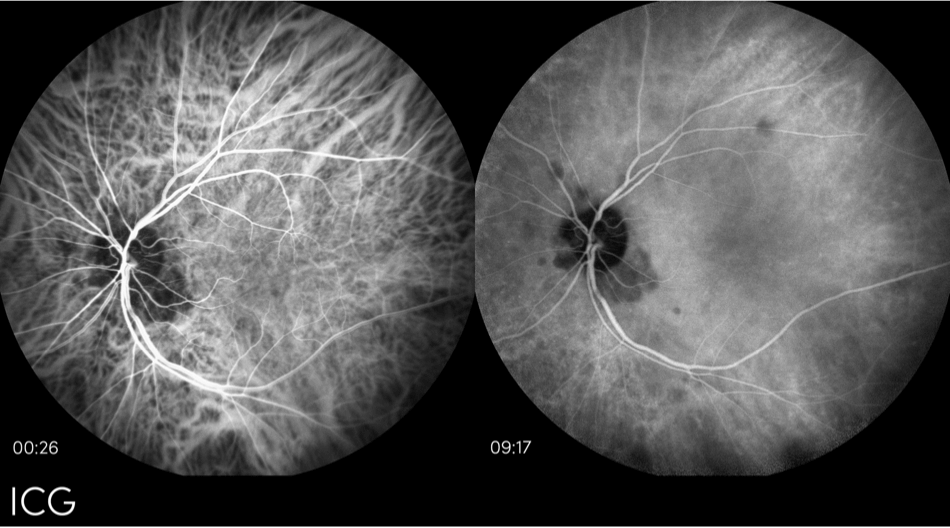

Indocyaningrün (ICG)-Angiographie

Die ICG ist ein bildgebendes Verfahren, das verwendet wird, um eine feuchte AMD auszuschließen. Außerdem werden damit atrophische Läsionen bei fortgeschrittener trockener AMD oder GA beurteilt.13 Die ICG-Angiographie funktioniert nach dem gleichen Prinzip wie die Fluoreszenz des Augenhintergrunds. Auch bei dieser Methode wird Licht auf die Netzhaut gestrahlt, um eine Fluoreszenz hervorzurufen. Bei der ICG-Angiographie wird jedoch ein Farbstoff in den Blutkreislauf injiziert, der eine bessere Bildauflösung ermöglicht.13